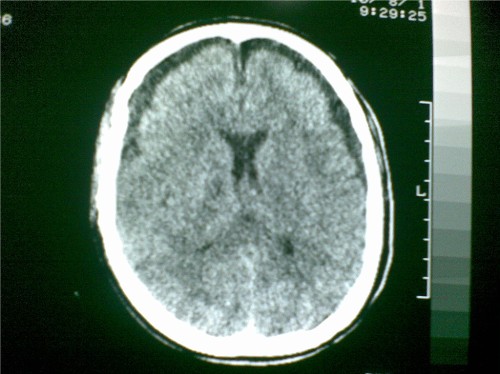

标题: CT28096:男,75岁,外伤10天后,现在恶心、呕吐。是硬膜下积 [打印本页]

标题: CT28096:男,75岁,外伤10天后,现在恶心、呕吐。是硬膜下积

硬膜下积液、右侧基底节、左侧放射冠腔梗。

硬膜下积液、多发性腔梗。

1)双侧额颞顶部硬膜下积液;建议必要时复查。2)多发性腔隙性脑梗塞。